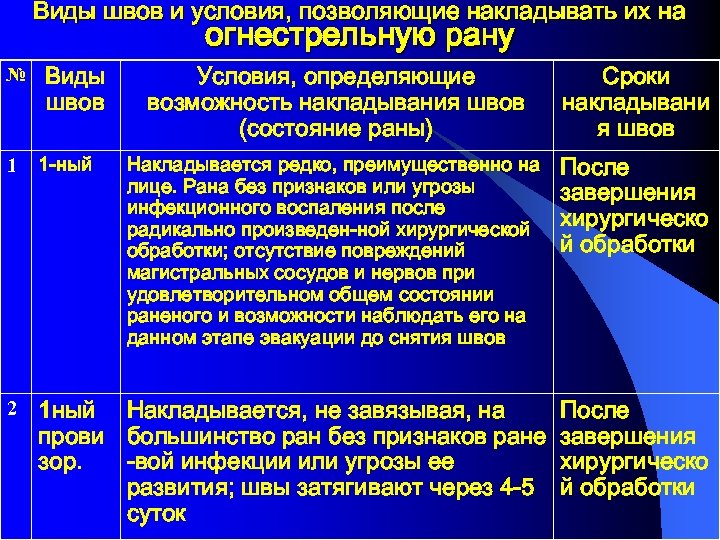

Виды швов и условия, позволяющие накладывать их на огнестрельную рану № Виды швов Условия, определяющие возможность накладывания швов (состояние раны) Сроки накладывани я швов Накладывается редко, преимущественно на лице. Рана без признаков или угрозы инфекционного воспаления после радикально произведен-ной хирургической обработки; отсутствие повреждений магистральных сосудов и нервов при удовлетворительном общем состоянии раненого и возможности наблюдать его на данном этапе эвакуации до снятия швов После завершения хирургическо й обработки 1 1 -ный 2 1 ный Накладывается, не завязывая, на прови большинство ран без признаков ране зор. -вой инфекции или угрозы ее развития; швы затягивают через 4 -5 суток После завершения хирургическо й обработки

Виды швов и условия, позволяющие накладывать их на огнестрельную рану № Виды швов Условия, определяющие возможность накладывания швов (состояние раны) Сроки накладывани я швов Накладывается редко, преимущественно на лице. Рана без признаков или угрозы инфекционного воспаления после радикально произведен-ной хирургической обработки; отсутствие повреждений магистральных сосудов и нервов при удовлетворительном общем состоянии раненого и возможности наблюдать его на данном этапе эвакуации до снятия швов После завершения хирургическо й обработки 1 1 -ный 2 1 ный Накладывается, не завязывая, на прови большинство ран без признаков ране зор. -вой инфекции или угрозы ее развития; швы затягивают через 4 -5 суток После завершения хирургическо й обработки

3 1 -ный отсроч. Накладывается до развития грануляций; рана без признаков инфекционного воспаления На 6 -7 сутки 4 2 -ный ранний На 815 сутки 5 2 -ный поздн. Накладывается на гранулирующую рану без признаков глубокой раневой инфекции при удовлетворительном состоянии раненого Накладывается на рану в стадии рубцевания. Рубцы и грануляции иссекаются, края раны мобилизуются для последующего сближения швами На 2030 сутки

3 1 -ный отсроч. Накладывается до развития грануляций; рана без признаков инфекционного воспаления На 6 -7 сутки 4 2 -ный ранний На 815 сутки 5 2 -ный поздн. Накладывается на гранулирующую рану без признаков глубокой раневой инфекции при удовлетворительном состоянии раненого Накладывается на рану в стадии рубцевания. Рубцы и грануляции иссекаются, края раны мобилизуются для последующего сближения швами На 2030 сутки